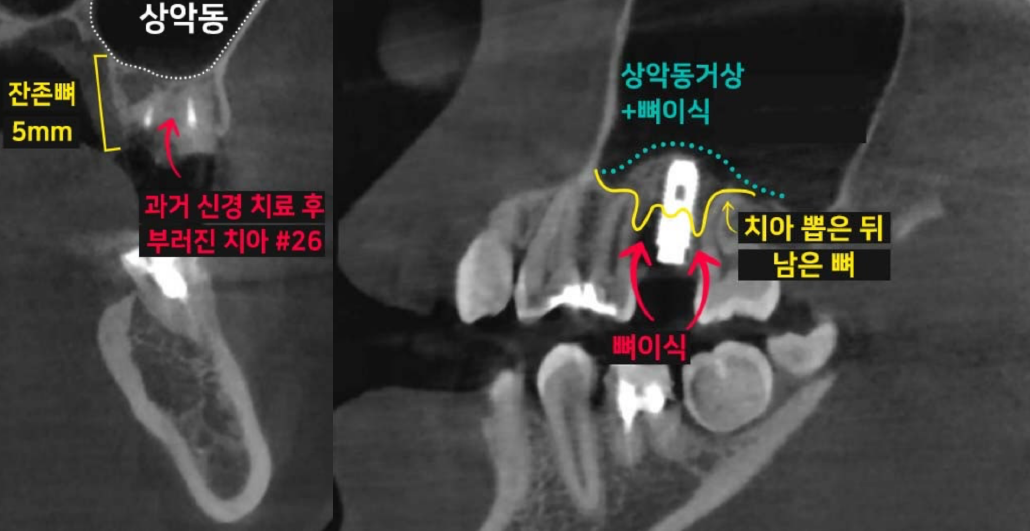

치아 손상으로 발치를 해야 할 때, '과연 바로 임플란트 시술이 가능할까?' 걱정하시는 분들이 많습니다. 이백점치과는 최신 의학 기술과 풍부한 임상 경험을 바탕으로 발치와 동시에 임플란트를 식립하는 것은 물론, 복잡한 케이스까지 성공적으로 진행하여 환자분들의 치료 기간과 불편함을 최소화하고 있습니다. ✨발치 동시 임플란트, 무엇이 다를까요? •일반적인 임플란트 식립: 치아를 발치한 후 잇몸과 뼈가 완전히 아물 때까지 약 3~4개월을 기다린 뒤 임플란트 를 식립합니다. 이후 임플란트와 뼈가 유착되는 데 3~4개월이 추가로 소요되며, 그 후에야 최종 보철물로 식사가 가능해집니다. 이 경우 치아가 없는 상태로 지내는 기간이 길어져 불편함을 느낄 수 있습니다. •이백점치과의 발치 동시 임플란트: 발치와 동시에 임플란트를 식립함으로써 치료 단계를 줄이고, 임플란트가 뼈와 유착되는 3~4개월 후에는 바로 최종 보철물(크라운)을 올려 즉시 식사가 가능합니다. 이를 통해 전체 치료 기간과 환자분의 불편감을 획기적으로 줄일 수 있습니다. CASE. 30대 여성 환자"이가 부러졌어요" ○ 환자분의 고민: 왼쪽 위 치아가 부러지고 염증이 생겨 임플란트를 희망하며 내원하셨습니다. ○ 진단: 파노라마와 CT 촬영 결과, 치아 뿌리만 남아있는 상태였고, 더 이상 치아를 살릴 수 없어 발치가 필요했습니다. 임플란트를 심을 수 있는 뼈가 5mm 정도로 부족하여, 일반적인 길이의 임플란트 식립을 위해 상악동거상술(뼈이식)이 동반되어야 하는 고난이도 케이스였습니다. ○ 치료 계획: 발치 후 즉시 임플란트 식립 & 상악동거상술 및 뼈이식 동시 진행  이백점치과의 정교한 발치 동시 임플란트 과정 과거에는 치아를 뽑고 3~4개월을 기다려야 임플란트 식립이 가능하다고 알려져 있었습니다. 하지만 이백점치과 는 다음과 같은 정교한 술식을 통해 발치와 동시에 임플란트 식립 및 뼈이식까지 가능하게 합니다. 1. 정확한 발치: 기존 뼈를 최대한 보존하며 잔존 치근과 치근단 염증을 완벽하게 제거합니다. 2. 이상적인 임플란트 식립: 환자분의 교합과 잔존 뼈를 고려하여 가장 이상적인 위치와 각도로 임플란트를 식립합니다. 3. 동시 뼈이식 및 상악동 거상술: 뼈가 부족한 부위에는 충분한 뼈이식을 진행하며, 특히 위턱 어금니 부위는 상악동 막을 안전하게 들어 올리는 상악동 거상술을 동시에 시행하여 임플란트가 단단하게 고정될 수 있는 기반을 마련합니다. 4. 깔끔한 잇몸 봉합: 빠르고 안정적인 치유를 위해 섬세하고 정확하게 잇몸을 봉합합니다.  빠른 회복과 뛰어난 예후: 믿을 수 있는 이백점치과 수술 직후부터 빠른 회복 과정을 보이는 것은 정확한 수술과 봉합 덕분입니다. 3개월 후 파노라마 사진에서도 상악동이 깨끗하고 뼈이식 부위가 자기 뼈로 잘 대체되고 있음을 확인할 수 있었습니다.  이처럼 발치 후에도 바로 임플란트 식립이 가능하며, 상악동 거상술과 뼈이식까지 동시에 진행될 수 있습니다. 이백점치과는 다양한 임상 경험을 바탕으로 고난이도 케이스도 성공적으로 이끌어내고 있으며, 수술 결과와 예후 로 환자분들께 신뢰를 증명하고 있습니다. |